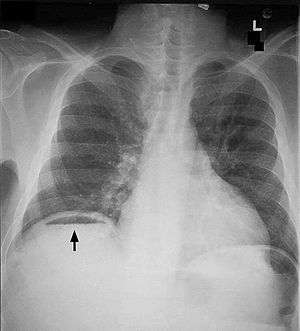

| Frontal chest X-ray. The air bubble below the right hemidiaphragm (on the left of the image) is a pneumoperitoneum. | |

Pneumoperitoneum is pneumatosis (abnormal presence of air or other gas) in the peritoneal cavity, a potential space within the abdominal cavity. When present, it can often be seen on radiography, but small amounts are often missed, and CT scan is nowadays regarded as a criterion standard in the assessment of a pneumoperitoneum.[1] CT can visualize quantities as small as 5 cm³ of air or gas. The most common cause is a perforated abdominal viscus, generally a perforated peptic ulcer, although any part of the bowel may perforate from a benign ulcer, tumor or abdominal trauma. A perforated appendix seldom causes a pneumoperitoneum.